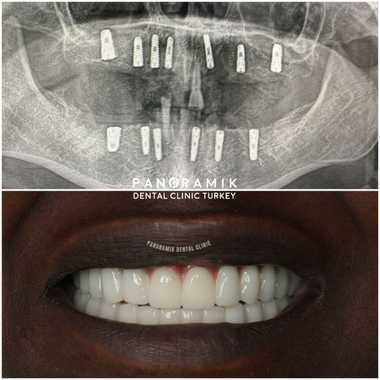

- It provides an aesthetically natural appearance.

Smile Time: Your smile will last for years with your teeth that have been used carefully and carefully and whose controls have not been interrupted. Take a look at our Before and after pictures.

In full mouth implant treatment, fixed prostheses are recommended because they are comfortable and look natural. However, removable prostheses can also be used depending on the patient's socioeconomic level, age, bone structure and systemic condition.